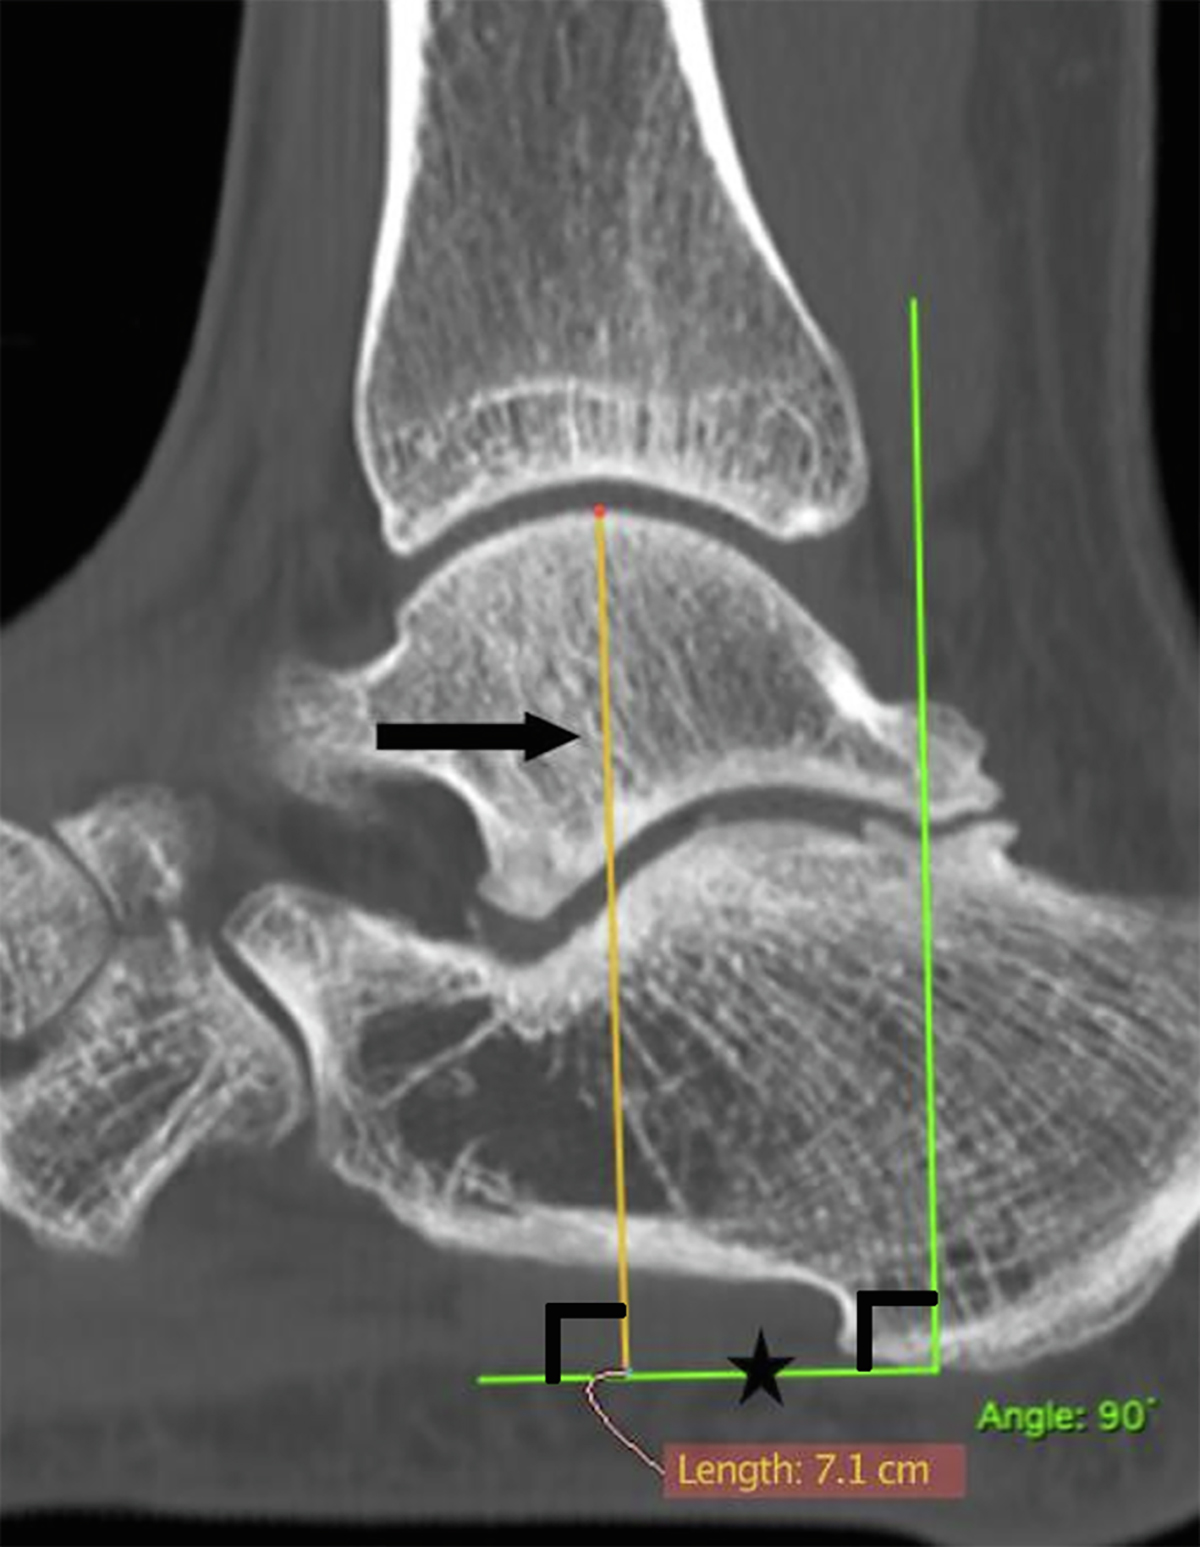

Preoperative hindfoot height (HFH) CT scan measurement. Plantar fascia, ⋆; HFH, → .